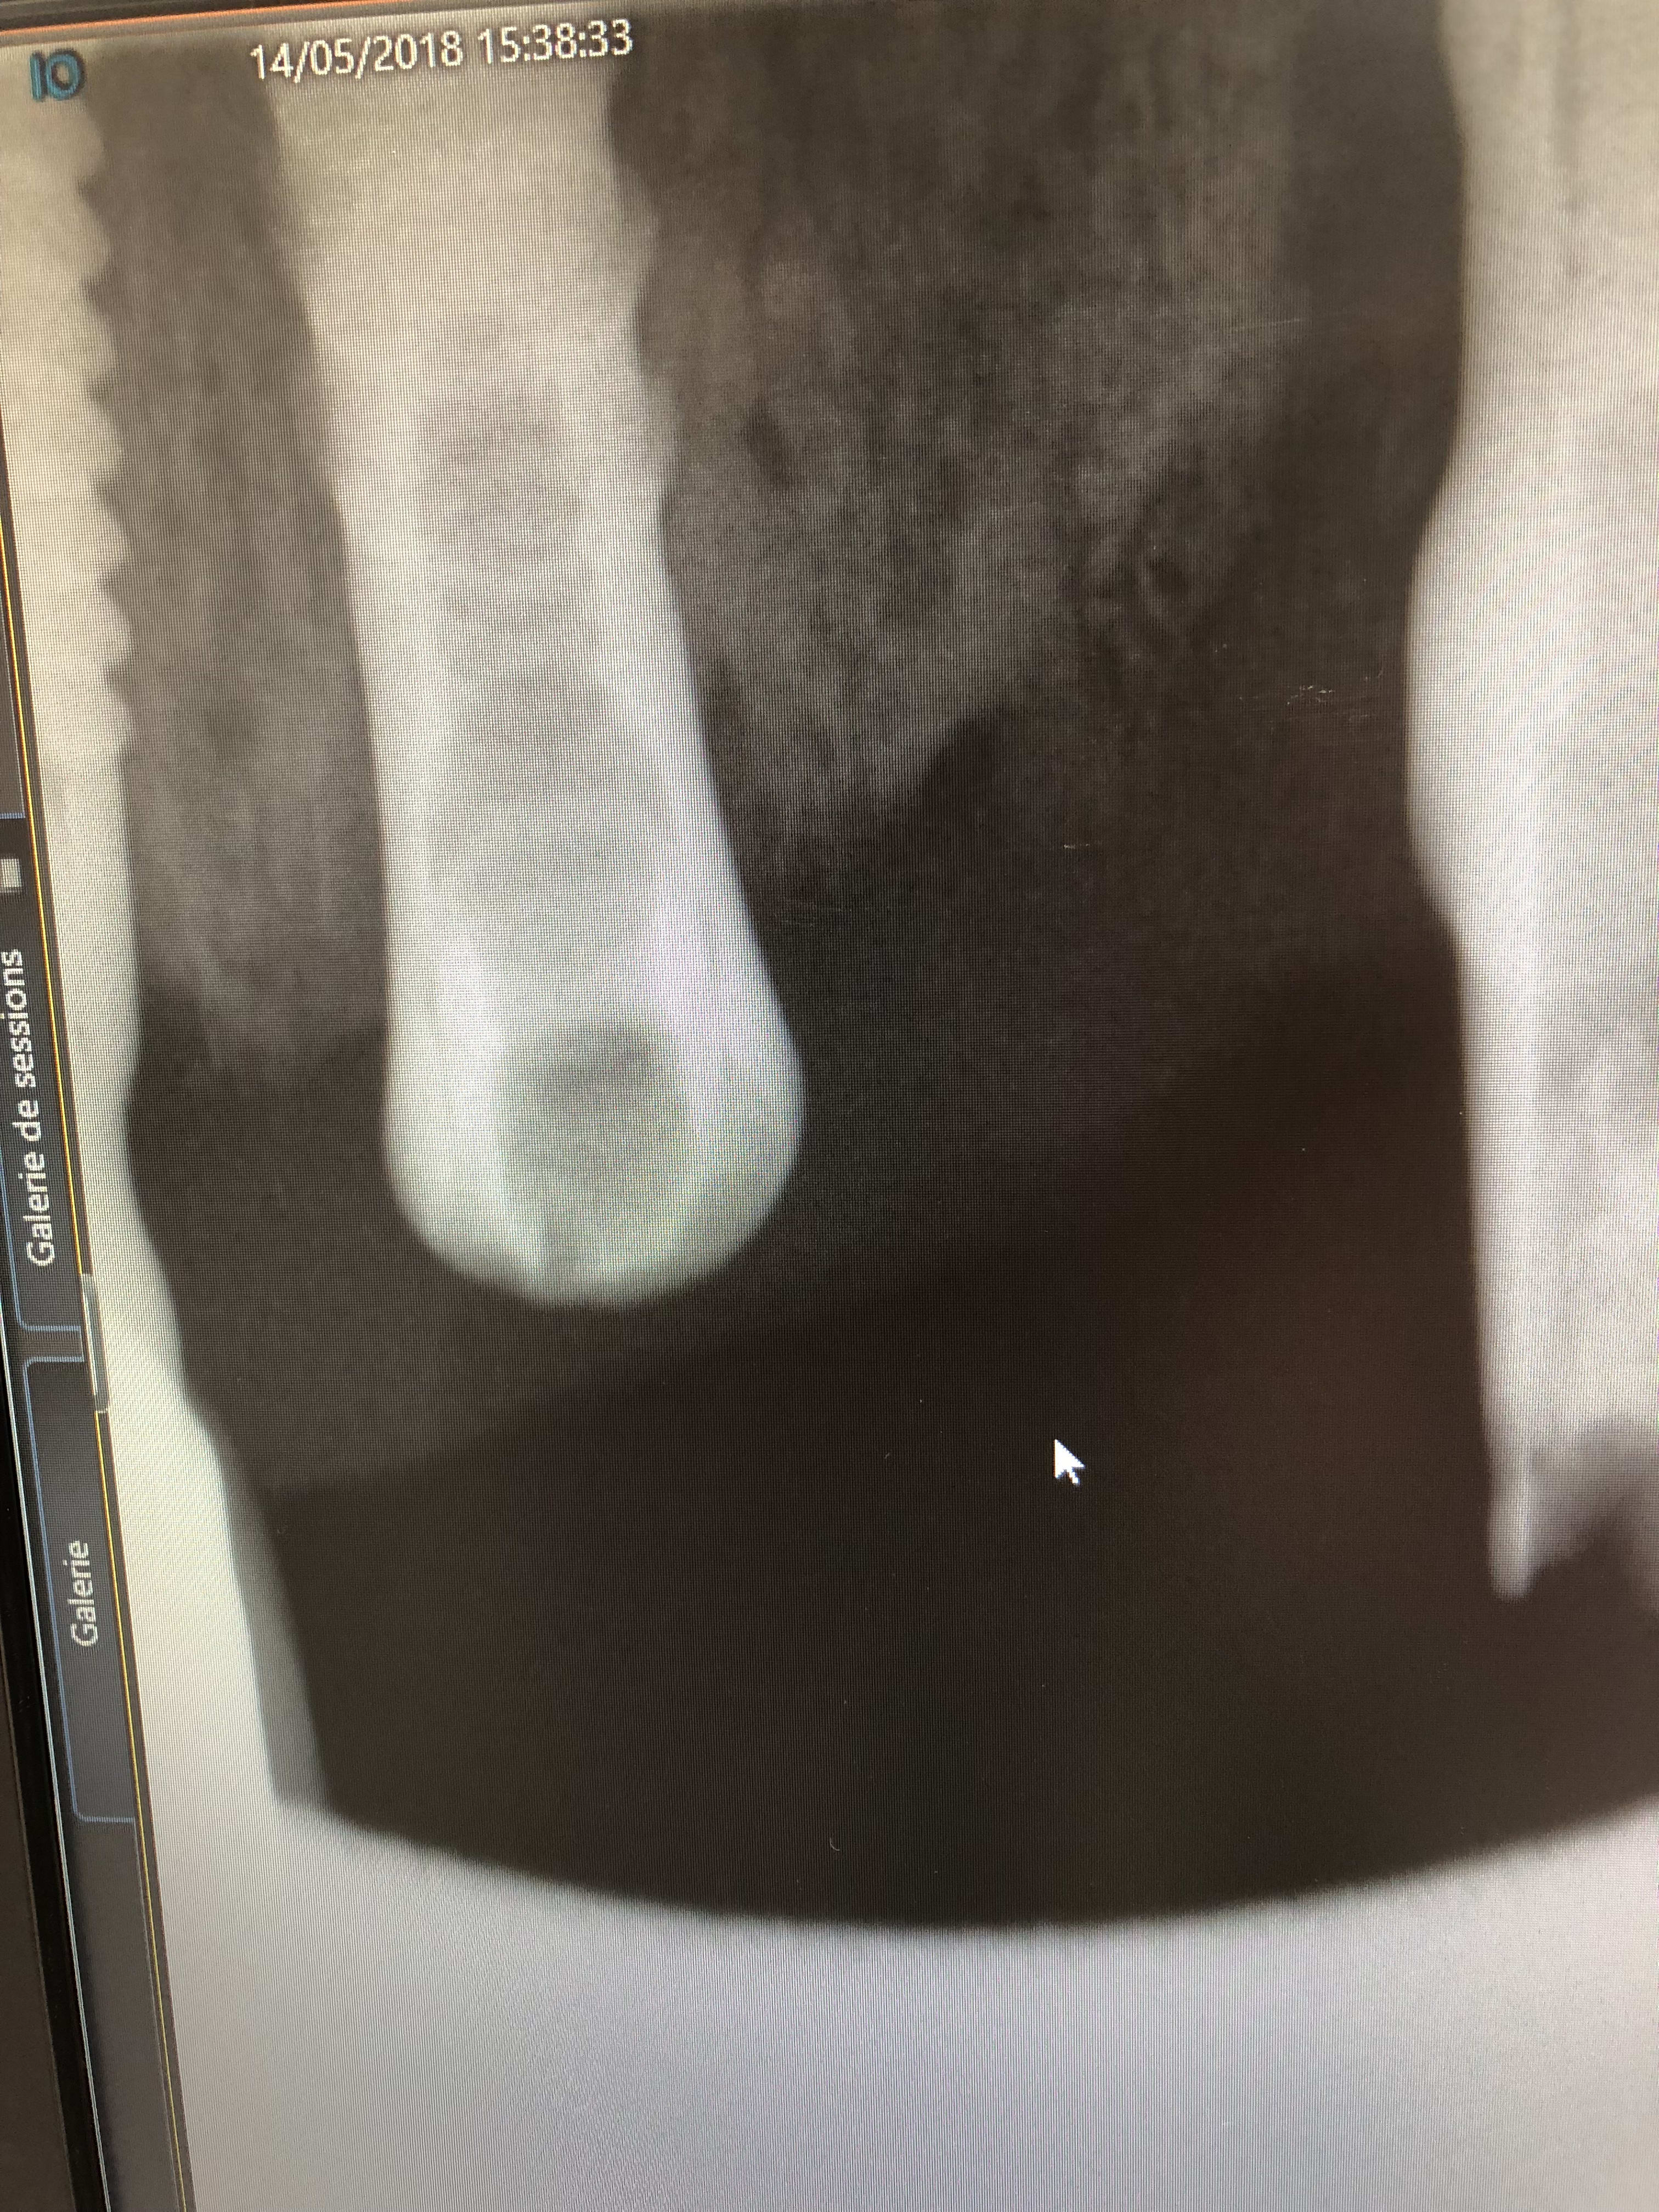

Je n’ai pas réussi à envoyer directement le cliché par mail mais je pense que la radio est meilleure..

donc oui c'est à 100% un Straumann

par contre tu as un morceau de pilier cassé dedans...

il faudra le retirer